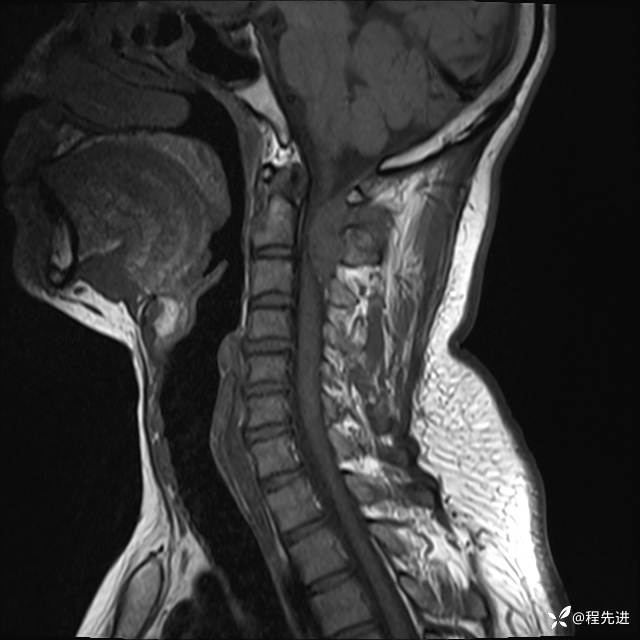

MRI平扫+增强:

T1:

T1增强: